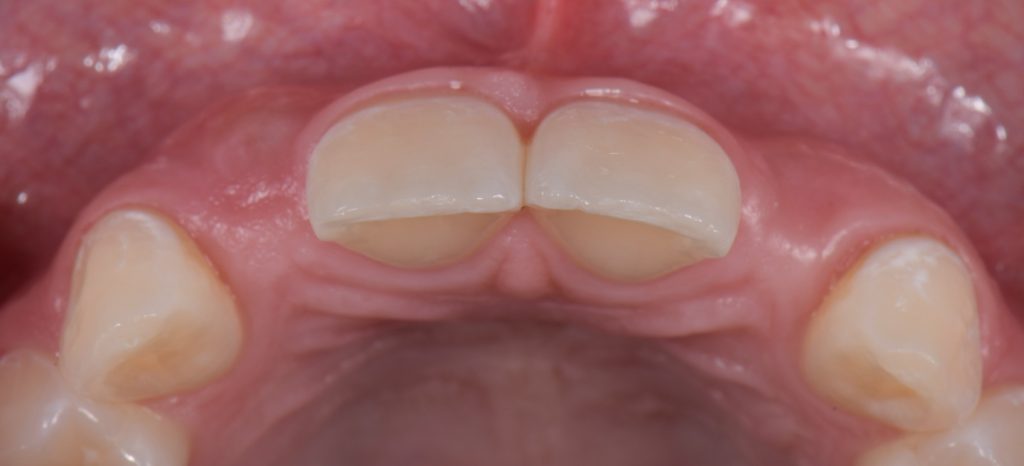

The undersized canines were out of function, removing all protective coverage for the lateral incisors. This provided a unique opportunity and indication for the most conservative scenario of a cantilevered RBFDP.

When considering a zirconia crown, we needed to ensure there was sufficient room for the wall thickness to be a minimum of 0.3 mm (ideally between 1.0 mm and 1.5 mm), an incisal reduction of 2.0 mm, and a visible and continuous circumferential chamfer with a reduction of at least 0.5 mm at the gingival margin. The patient’s preliminary condition allowed us to accomplish these space requirements with hardly any tooth reduction (Fig. 17).

RBFPD has an exceptional record, so this cantilever bridge can be considered a long-term solution. However, if in the future an implant-supported restoration is desired, the pontic of this cantilever can be removed, and an implant could be placed and restored.